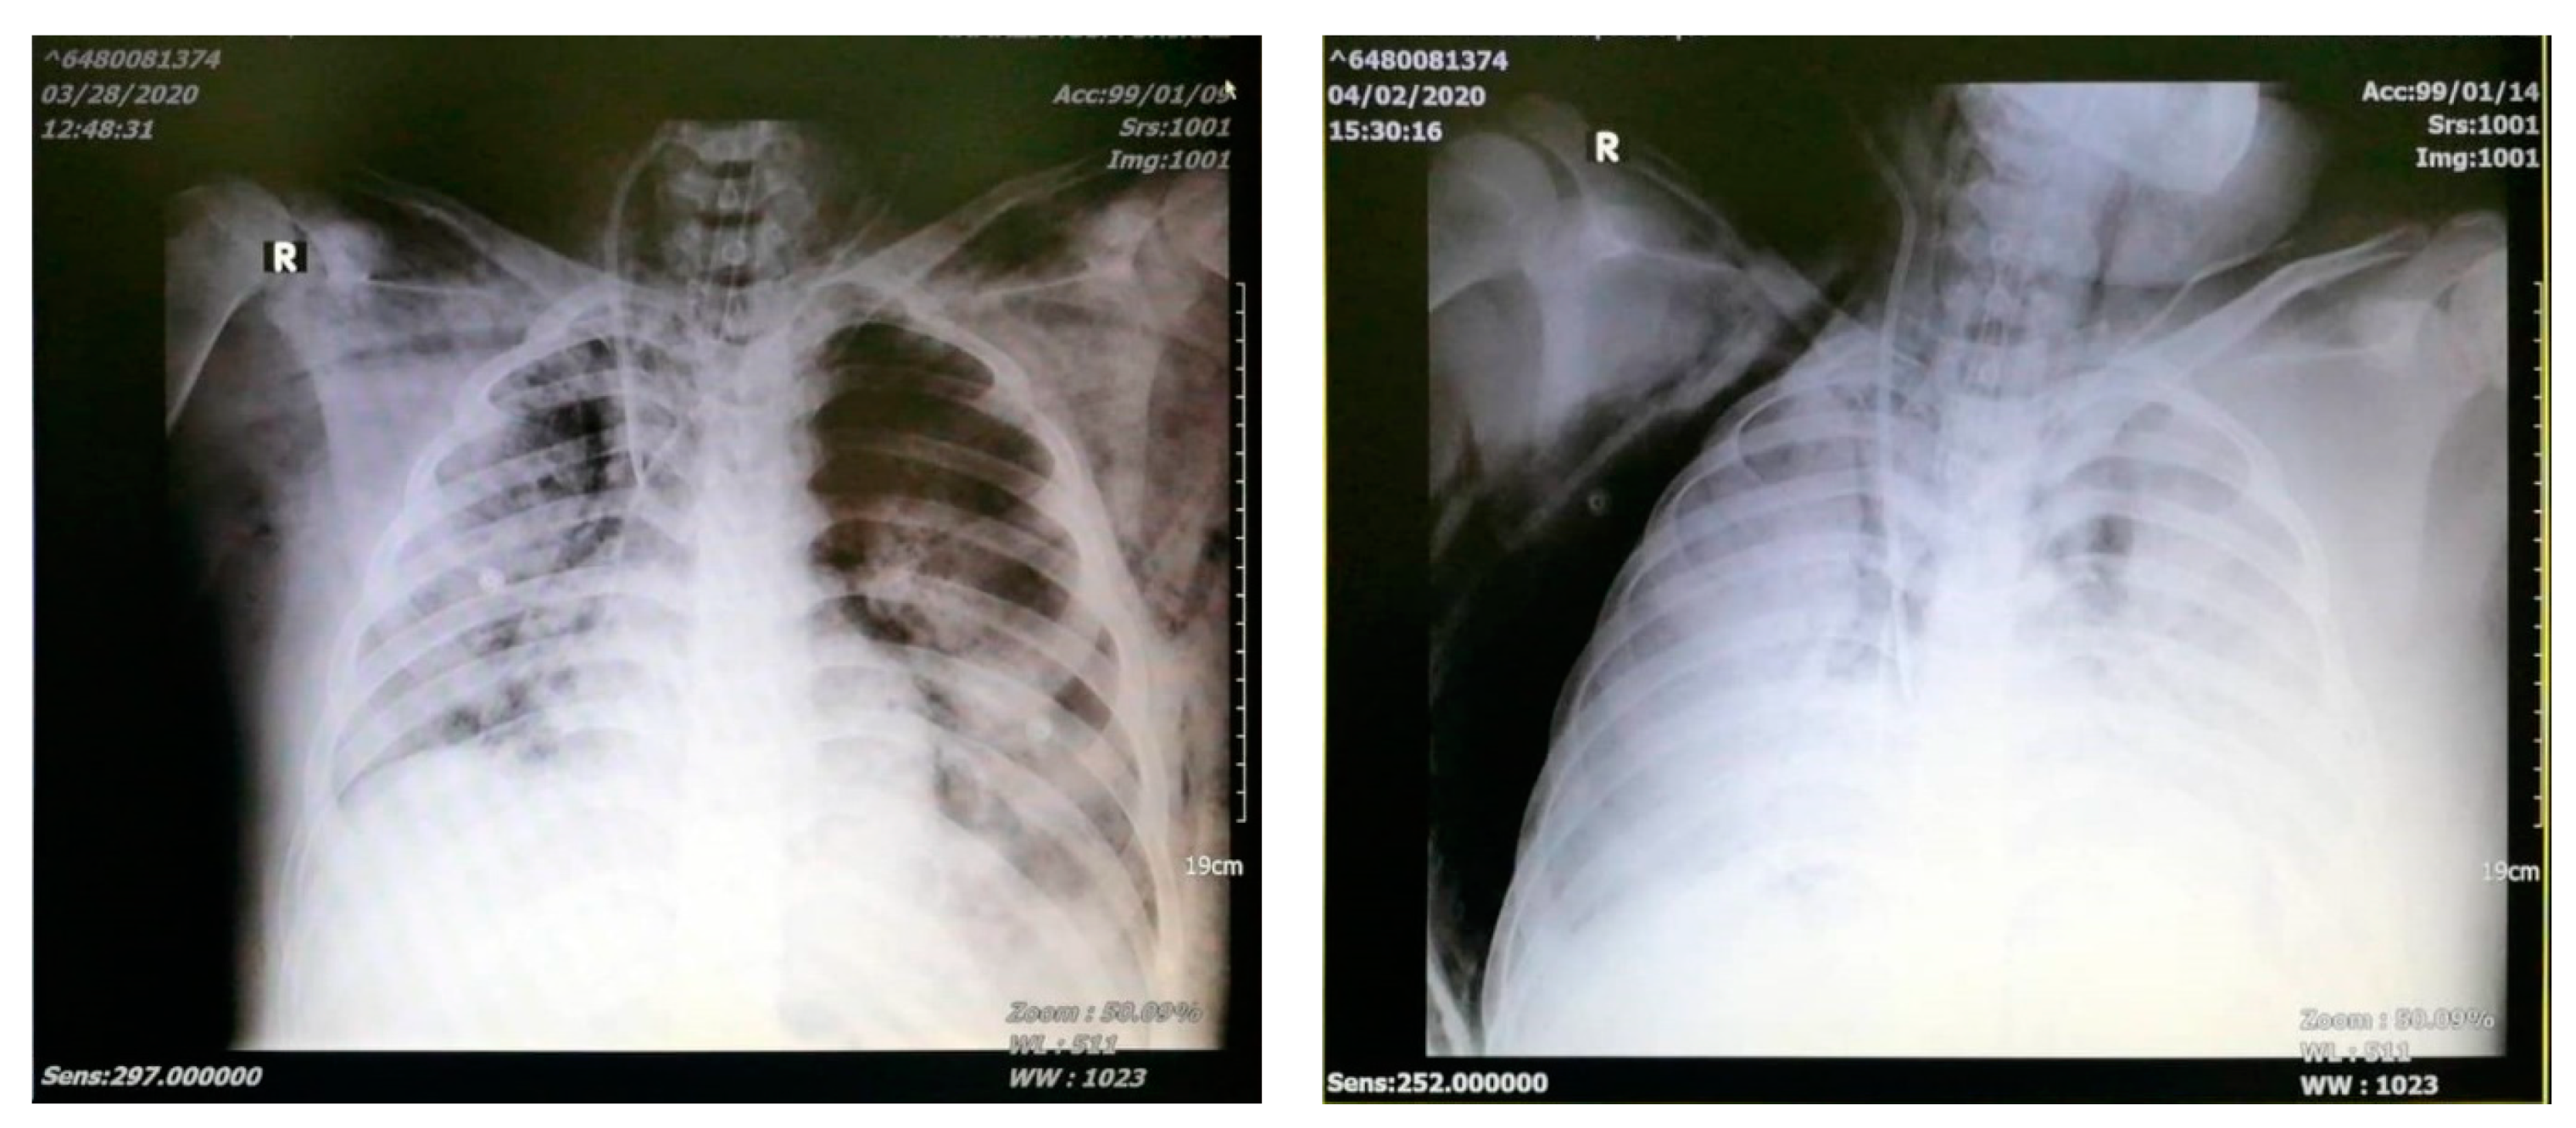

Chest X-ray on admission showed bilateral patchy infiltration which deteriorated to white lung on day 6 (Figure 1). A CT scan was not done due to his severe condition and the lack of a portable ventilator with high PEEP set up. All lab tests are shown in Table 1.

Figure 1.

Chest X-ray on day 1 (left) and day 4 (right).